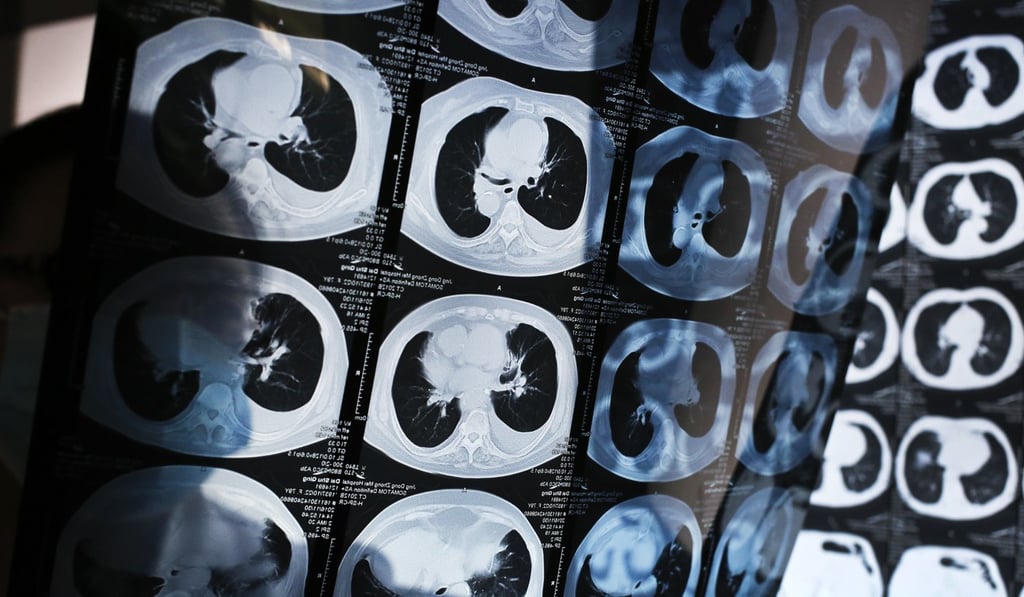

Air pollution suspected for sharp rise in China lung cancer rate

China has seen a sharp rise in the incidence of lung cancer in the past 10 to 15 years, with long-term exposure to air pollution a possible culprit, state media reported.

Experts with the China Academy of Medical Sciences said lung cancer was rising rapidly in groups not normally susceptible to the disease, including women and non-smokers, suggesting that smoking was not responsible for the increase, the China Daily said.

An estimated 300 million Chinese people are smokers, but the paper said there had been a rapid increase in a form of lung cancer that develops deep in the lung and is not associated with tobacco use.